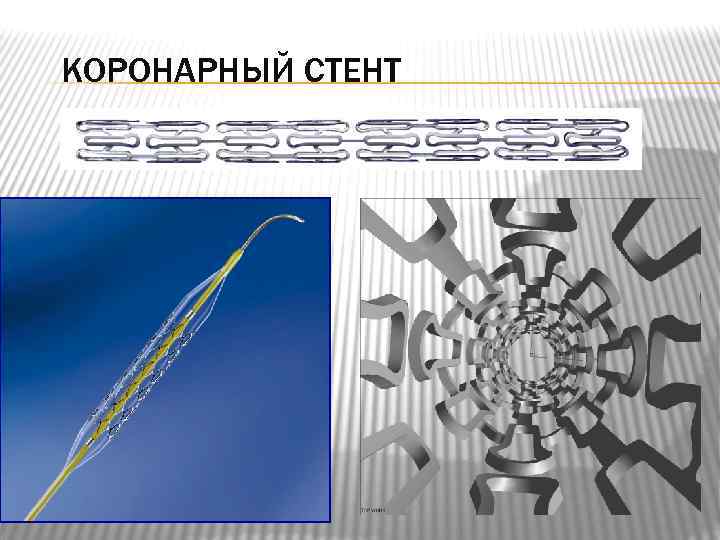

КОРОНАРНЫЙ СТЕНТ

КОРОНАРНЫЙ СТЕНТ